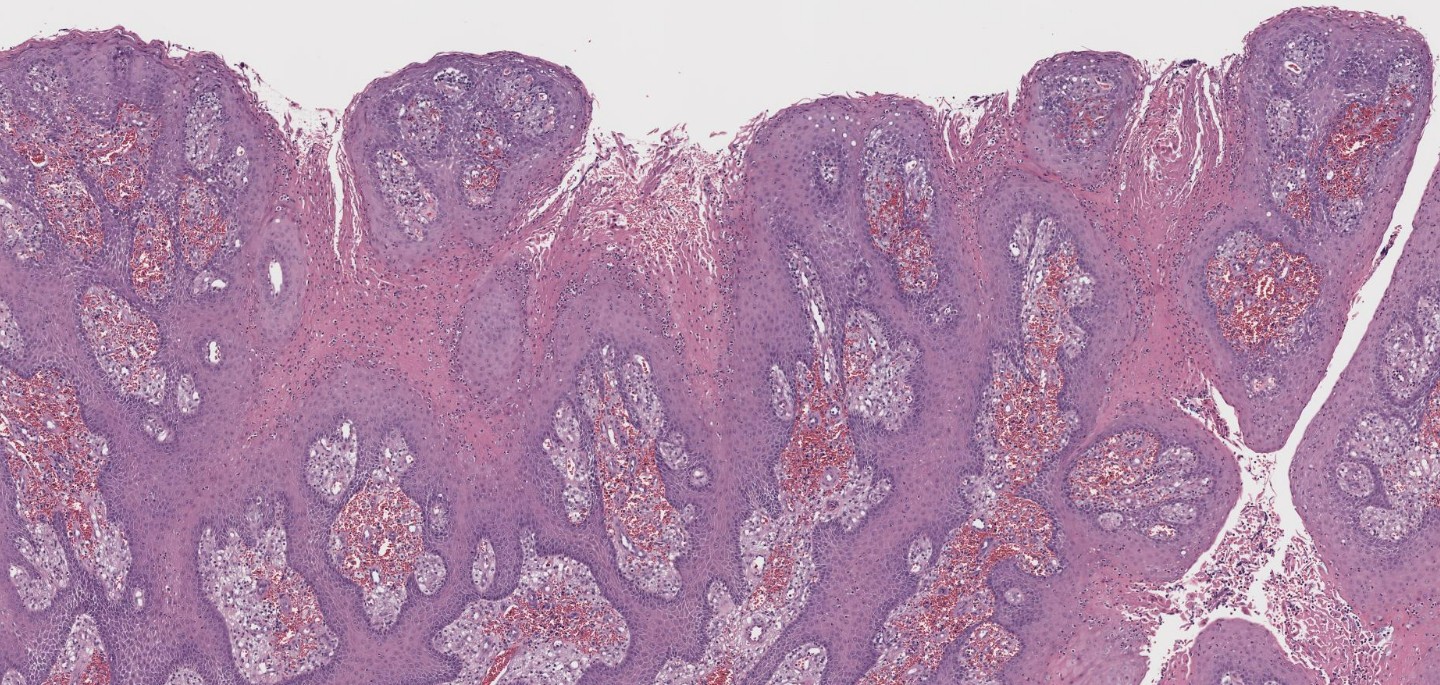

(Medium power showing papillomatosis)

On examination, several defining features stand out: